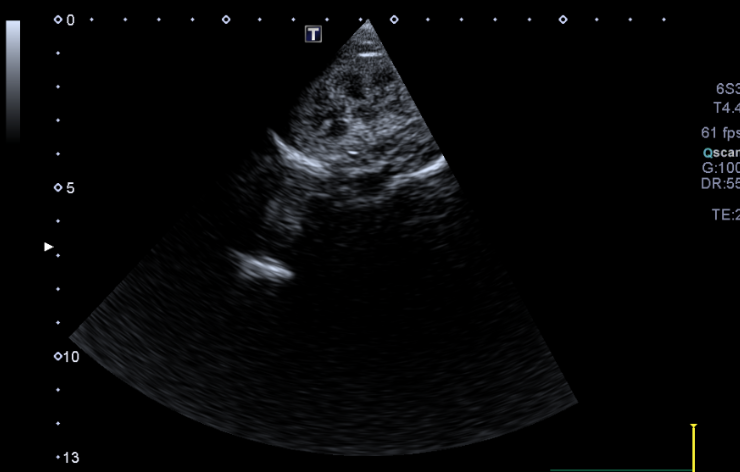

4 - Est ce que l’image obtenue vous semble correcte ?

A - Oui

B - Non

C - Je ne sais pas

5- Si non, expliquez quel réglage serait intéressant de modifier pour obtenir une image échographique correcte

A - J'ai coché oui à la réponse précédente

B - Diminuer la profondeur

C - Augmenter la profondeur

D - Augmenter le gain étagé en profondeur

E - Diminuer le gain étagé en profondeur

Question 4 : Réponse B

Question 5 : Réponse B